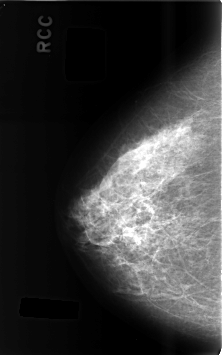

Digital Database for Screening Mammography

Volume: benign_13 Case: C-0487-1

C_0487_1.RIGHT_CC

RIGHT_CC LINES 4608 PIXELS_PER_LINE 2880 BITS_PER_PIXEL 12 RESOLUTION 50 NON_OVERLAY